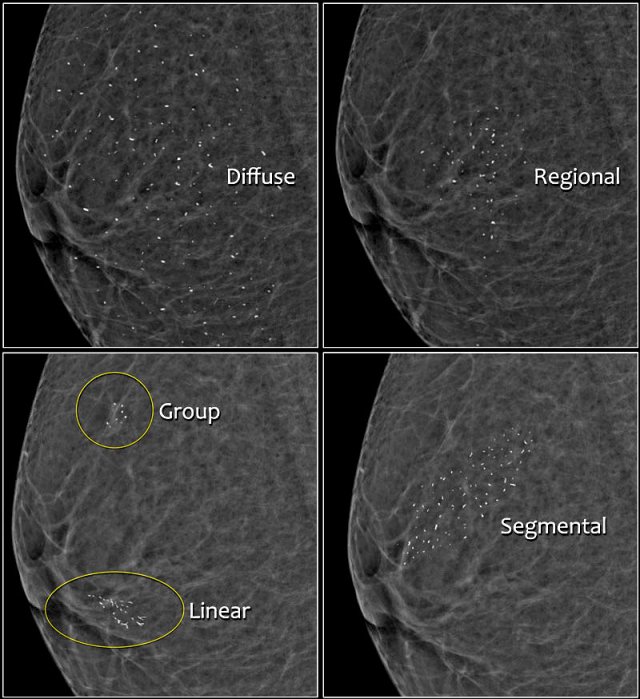

Distribution of calcifications

The arrangement of calcifications, the distribution, is at least as important as morphology.

These descriptors are arranged according to the risk of malignancy:

- Diffuse: distributed randomly throughout the breast.

- Regional: occupying a large portion of breast tissue > 2 cm greatest dimension

- Grouped (historically cluster): few calcifications occupying a small portion of breast tissue: lower limit 5 calcifications within 1 cm and upper limit a larger number of calcifications within 2 cm.

- Linear: arranged in a line, which suggests deposits in a duct.

- Segmental: suggests deposits in a duct or ducts and their branches.

The 2013 edition refines the upper limit in size for grouped distribution as 2 cm (historically 1 cm) while retaining > 2 cm as the lower limit for regional distribution.